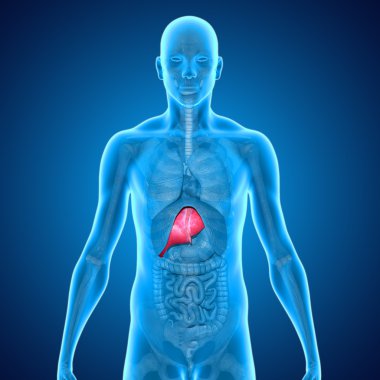

İnsan vücudundaki böbreklerin hologramı. Geleceğin sağlık hizmetleri. Modern tıp bilimi. 3B illüstrasyon, 3B canlandırma

ArkaplanresimlemeİnsanSağlıksağlıklıİlaçSağlık hizmetleriHastalıkTıbbidikkatteknolojiçizgi filmGeleceğe yönelikDoktorHastaneAygıtDijitalgövdeterapiTedavibiyolojiBilimkanserSistemGözlüklerAcıYenilikorgKulaklıktaşlaranatomiklinikİşlemOrgan nakliBöbreklerBöbrekHologramçokgenÜroloji3d oluşturma3B illüstrasyonpiyelonefritBenzer İçerikler